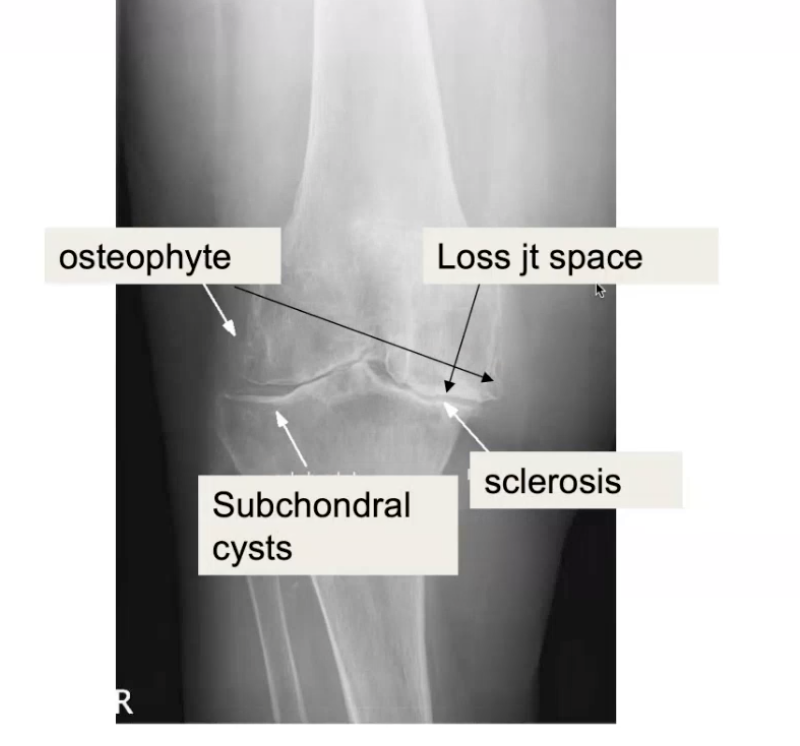

Q

What are the radiographic changes of OA?